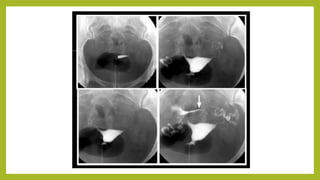

Se obtienen 4 radiografía después de la imagen

Se obtienen 4radiografía después de la imagen panorámica seguidas por fluoroscopia, para evaluar útero (cavidad endometrial) y trompas

Se comienza ainstilar lentamente el contraste, se aprecian mejor defectos de llenado o del contorno

Útero totalmente distendidopara mejor evaluación de la forma

Demostrar y evaluarlasTrompas de Falopio

Derrame libre decontraste intraperitoneal